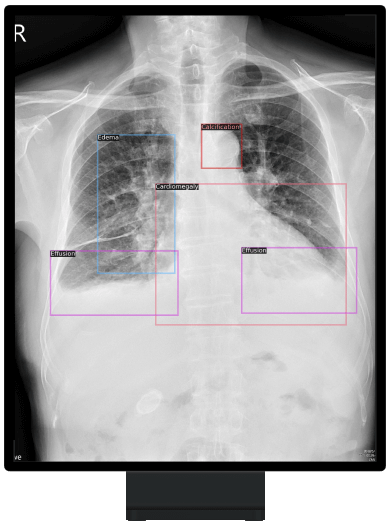

提供心、肺、骨骼等15項相關病徵偵測,輔助醫師在龐大影像數量下進行快速判讀,有助於醫師作出快速診斷與決策,提高醫療照顧品質